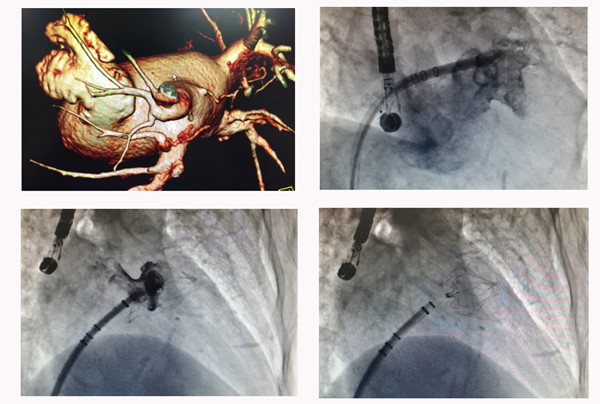

参赛病例|左心耳双伞封堵一例

术前左心耳ct重建左心耳形态

左心耳ct及造影

术前cta:左心耳开口切面利用ct数据三维重建获悉,左心耳开口长轴26.